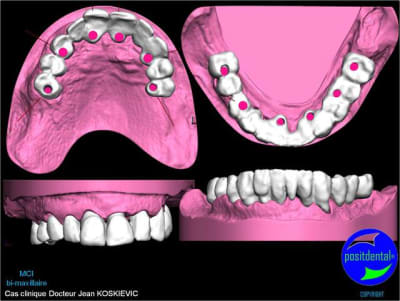

Je viens de recevoir les empreintes pour réaliser un Positscan en prévision d'une MCI bi-maxillaire. "chouette" un peu de métal pour corser l'histoire.

Montage esthétique ou wax-up 3D

et la projet 10 implants maxillaire sup